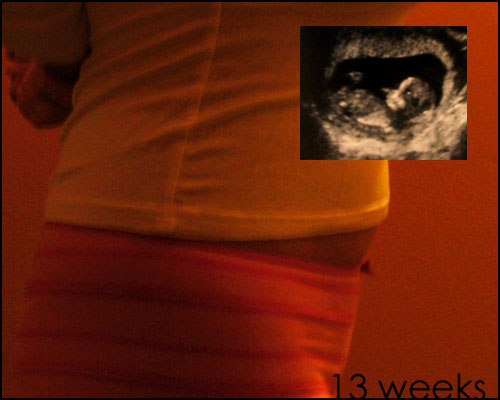

Yesterday I went back for the second ultrasound, and I did not drink nearly as much water beforehand because I have Learned My Damn Lesson when it comes to bladder capacity and waiting rooms. This time, there was no need for wacky gymnastics designed to shake the bebe into a better position, he or she cooperated right off the bat and the test only took a few minutes.

(Oh, and during our first appointment, she estimated the due date at Sept. 18, not the 26th. So I'm a little further along than I thought. Huh.)

I don't really know how to describe how joyful, amazing, and overwhelming it is to watch that monitor and see the life inside me, one tiny hand near the mouth as though thumb sucking, the unmistakable image of the heart beat beat beating away. "Sorry you had to come back," the tech said when we were done. "You know, I really didn't mind," I said, still seeing the shape of our moving, growing baby.

Speaking of the belly, are you ready? For this particular jelly?